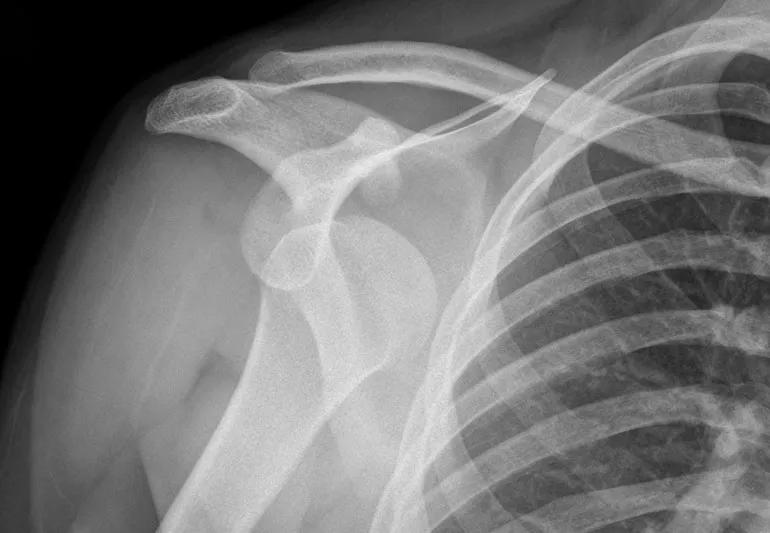

Can A Dislocated Shoulder Ever Heal . However, it may take several months for your. After surgery, you'll wear a sling for about six weeks, gradually working on range of motion and strength. When you dislocate your shoulder, a permanent change occurs where. Full recovery may take five to six months. After two weeks, you should be able to return most activities of daily living. Can a dislocated shoulder heal itself? How long will it take to heal? It can take anywhere from 12 to 16 weeks to completely recover from a dislocated shoulder. Separated shoulders may heal over a period of 6 weeks. It usually takes up to 12 weeks to recover from a dislocated shoulder. If your dislocation is fairly simple, your shoulder joint will improve over a few weeks. For most people the symptoms from a dislocation will settle down without any problems in six to twelve weeks. It may take up to 16 weeks to fully return to playing some sports, but for. You will be able to.